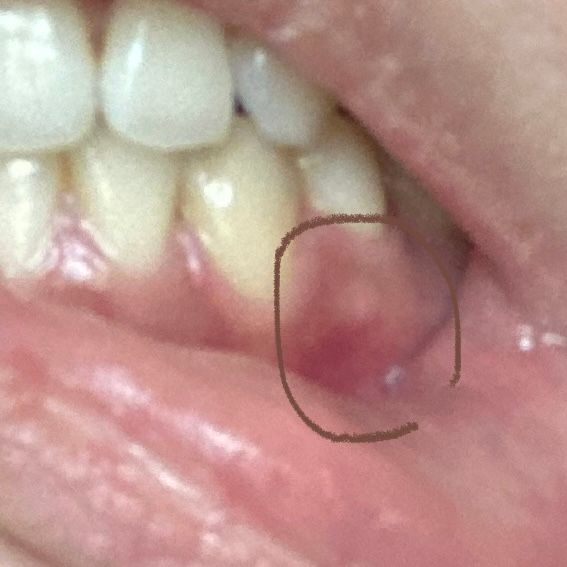

잇몸에 하얀 부분이요, 혹시 잇몸 염증 초기일까요?

사진에 표시된 흰 부분을 눌러보니 딱딱하고 아프진 않습니다.

그렇지만 저게 잇몸 염증이나 고름주머니의 초기 모습일까봐 너무 신경쓰이네요.

• 1번 째 사진